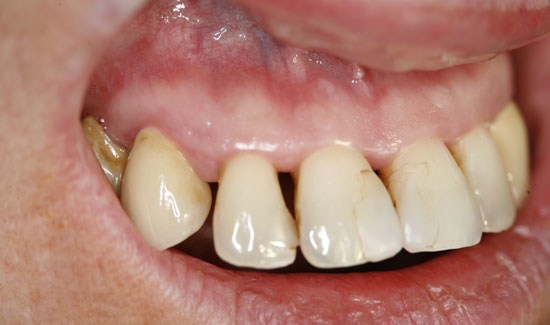

Фиг. 3: Състояние след терапията с озон. Хлорхексидиново оцветяване на зъбите